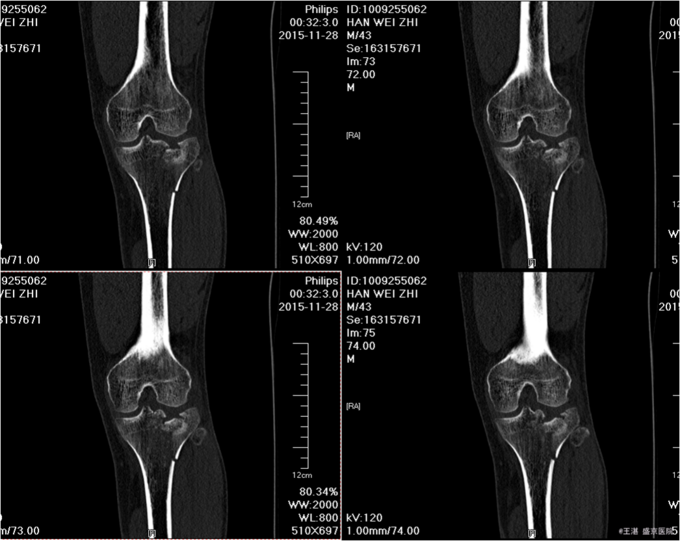

患者及家属自诉于2015年11月28日晚9点在沈阳市铁西区自己摔倒,摔倒后左下肢疼痛,活动受限,不能活动,急送至沈阳八院急诊,行DR提示:左胫骨近端粉碎性骨折。后送至我院急诊,行左膝关节CT后以“左胫骨近端粉碎性骨折”为主要诊断收入我科。患者轮椅入病房,无发热,无头晕头迷,无胸闷气短,无心慌心悸,无腹痛腹胀,受伤后排气正常,大小便未排。

专科查体:患者轮椅入病房。左小腿活动受限,压痛(+),叩击痛(+),双下肢皮肤感觉正常,足背动脉可扪及搏动,末梢血运良好,足趾活动灵活。 辅助检查:左膝关节CT:(我院,2015-11-29):左胫骨近端粉碎性骨折。